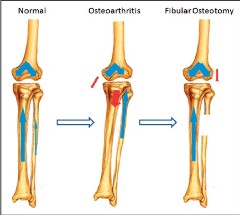

Подобно высокой остеотомии большеберцовой кости проксимальная корригирующая остеотомия малоберцовой кости может облегчить симптомы медиального остеоартроза с перестройкой нижней конечности. Однако, хотя исправление оси конечности является основной целью высокой остеотомии большеберцовой кости, принцип проксимальной корригирующей остеотомии малоберцовой кости исходит из теории «неравномерного распределения».

Как следствие поддержки малоберцовой костью, «неравномерный» означает, что давление на плато большеберцовой кости является асимметричным, причем давление на медиальном плато более выражено, чем на латеральном плато. В конце концов, медиальное плато становится значительно ниже латерального, и в нижней конечности возникает варусная деформация. Эти изменения механической оси приводят к концентрации напряжений в медиальном компартменте и дегенерации хряща и мениска, которые являются основными патологическими проявлениями медиального остеоартроза. Таким образом, при «неравномерном распределении большеберцовой кости» медиальный остеоартроз можно также назвать «синдромом дисбаланса в коленном суставе».

Проксимальная корригирующая остеотомия малоберцовой кости ослабляет боковую поддержку малоберцовой кости и приводит к коррекции варусной деформации, которая впоследствии может смещать направление нагрузки от медиального отдела в сторону латерального отдела, что приводит к уменьшению боли и удовлетворительному функциональному восстановлению.